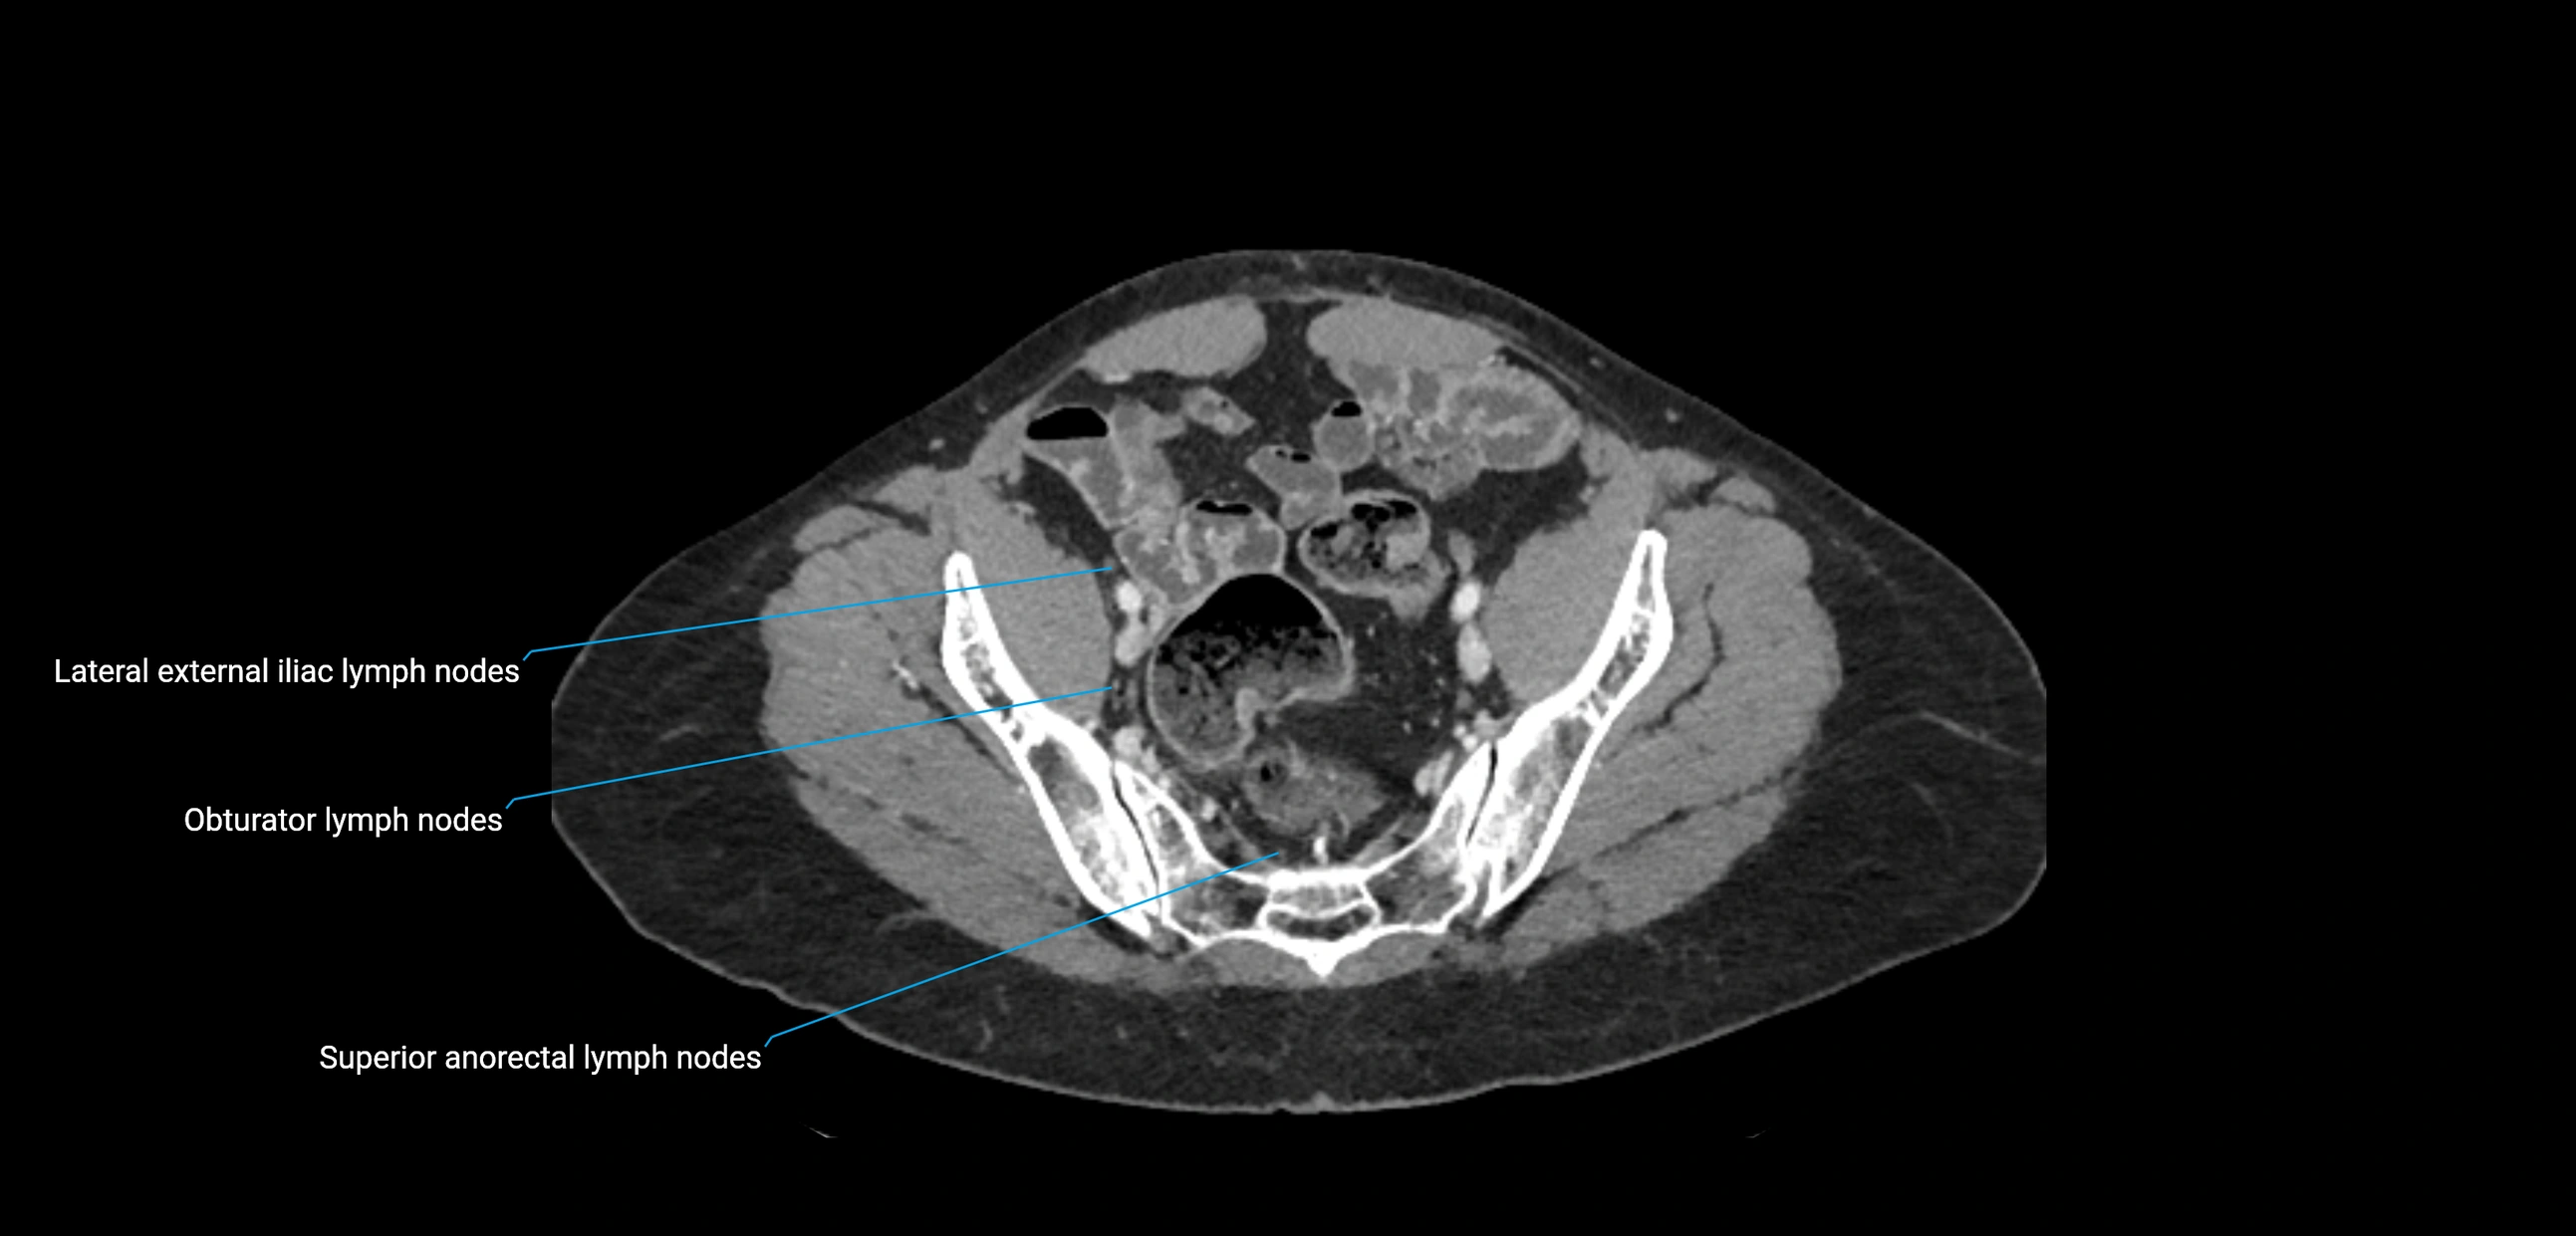

CT Appearance

CT Pre-Contrast:

• Nodes appear as soft-tissue density nodules adjacent to the aorta and IVC

• Calcification may be seen in chronic infections (e.g., tuberculosis)

CT Post-Contrast:

• Normal nodes enhance homogeneously

• Malignant nodes may show heterogeneous enhancement, central necrosis, or conglomerate formation

• Size >1 cm short axis is suspicious, though morphology and distribution are equally important

CT Venography (CTV):

• Demonstrates nodal encasement or compression of adjacent vessels (aorta, IVC, renal veins)

• Useful in staging testicular and ovarian malignancies

• Provides 3D reconstructions for retroperitoneal lymph node dissection planning